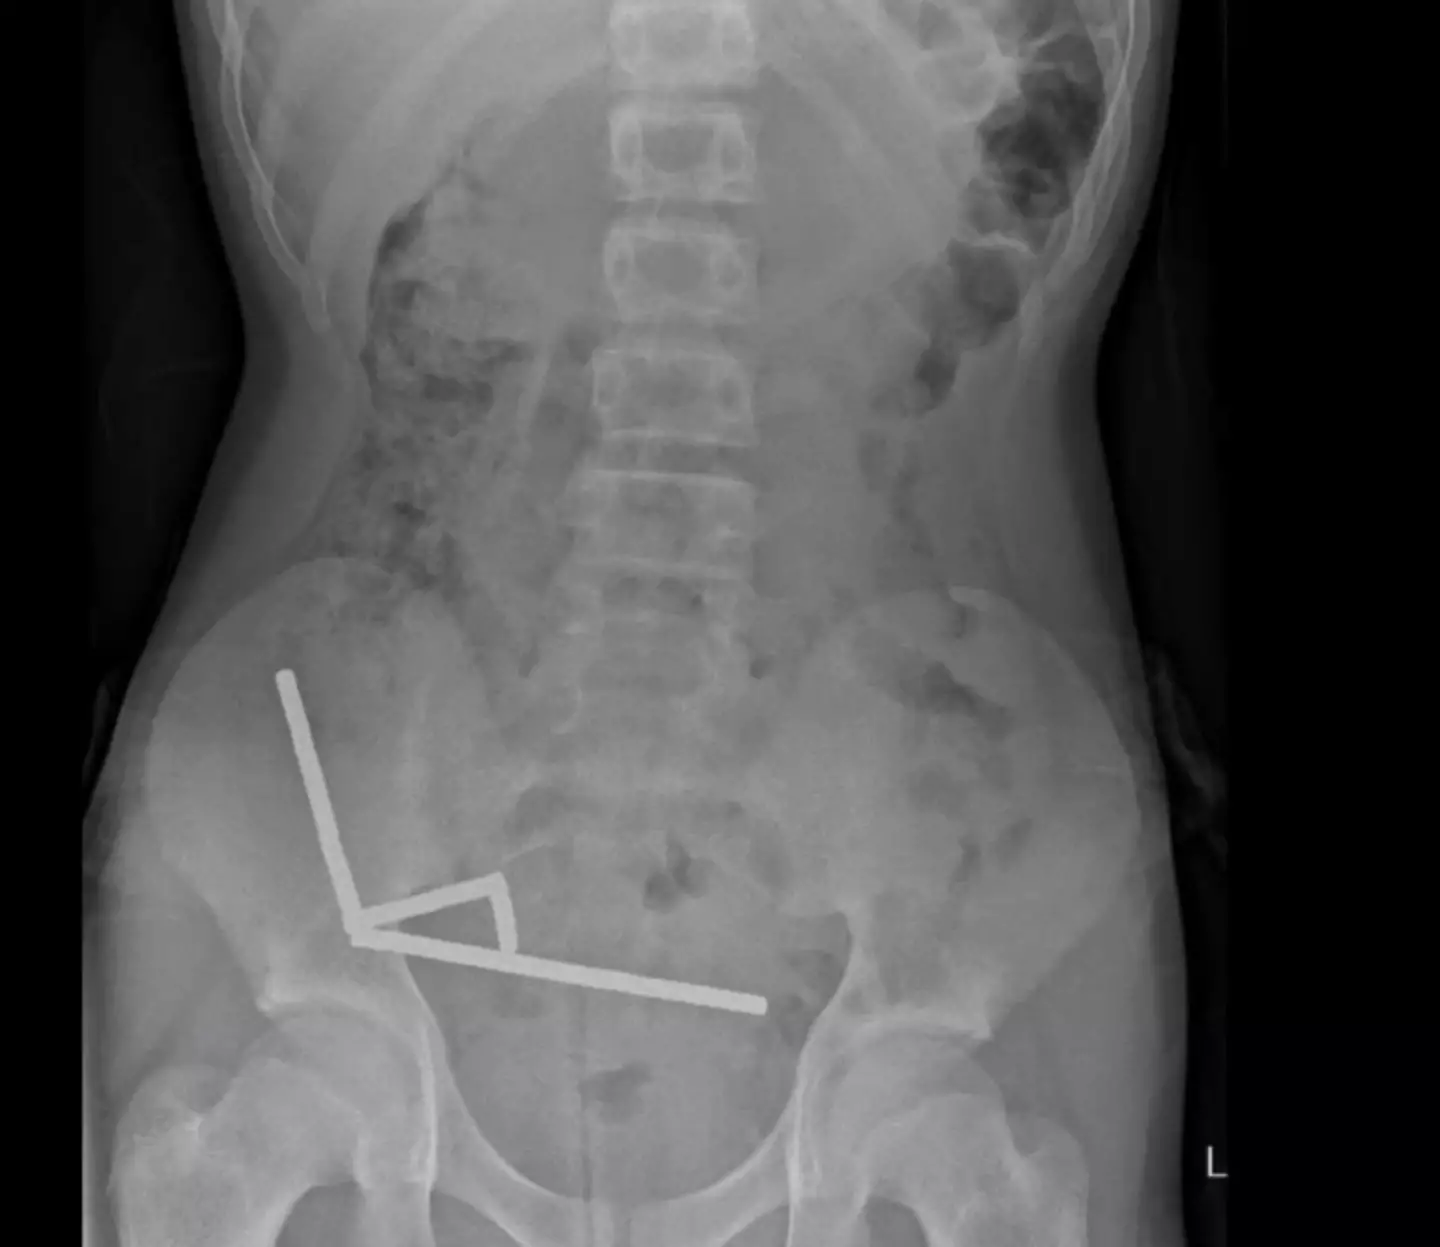

Imaging scans revealed four chains of tiny magnets, which were all 'in separate parts of bowel' but 'adhered together due to magnetic forces'.

The presence of the magnets within the bowel caused a health condition called 'pressure necrosis', in which tissues die due to prolonged pressure that compresses blood vessels and cuts off the oxygen supply.

Emergency surgery was required to remove the magnets as well as various sections of the bowel that were damaged.